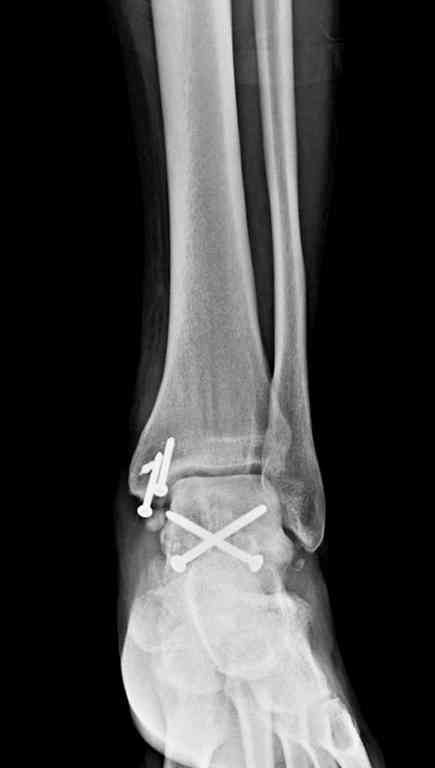

Вчера провели фиксацию.

Из-за многооскольчатости дистальной части малоберцовой, где невозможно было провести фиксацию шурупами, перелом зафиксирован подпирающей пластиной, которая должна служить дополнением отсутствующей дистальной части малоберцовой (lateral cortex substitute).

Для стабильности два шурупа на синдесмоз.

Медиальную рану с приближенными краями продолжаем вакуумировать (KCI). Наружный фиксатор оставлен на пару недель, надеюсь, небольшая рана будет гранулировать и закроется без кожной пластики. Фиксация медиальной ложыжки не планируется.